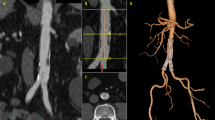

VRT overlay provided the projection of the target vessel on its entire length associated with target ostia vessel landmark represented as a ring (Fig. 1). It was used to select the optimal C-arm angulation during endovascular navigation. The generated 3D road map was synchronized with the C-arm/table positions in order to provide live update and to match the 2D-fluoroscopy at any C-arm/table angle, position and magnification. The image fusion accuracy was assessed at the beginning of each intervention with the control of the correct registration between the two image sets when the catheter was placed into the left renal artery.

This is a case of an in situ laser fenestration for two target vessels (superior mesenteric and right renal arteries); in this case, landmarks were placed at the ostia places of the celiac trunk, the superior mesenteric artery and the right renal artery. (The left kidney was atrophic and non functional.) First, the Aptus catheter was placed in front of the superior mesenteric artery based on image fusion coronal and sagittal views and the guide wire was placed into the target vessel after perforation, here the superior mesenteric artery (A). A cutting balloon was placed to enlarge the hole (B) followed by a balloon dilatation. A long sheath was placed into the target vessel (C) before the stent placement (D) and deployment (E). The Aptus catheter was then placed in front of the right renal artery on frontal and sagittal views before perforation (F)

On the one-week CTA, aneurysms were excluded and all target vessels were patents in 17 patients (efficacy: 85%). The same patient with the unsuccessful LISFAS for a renal artery described above had a minor type 3 endoleak, which was successfully embolized with coils during hospital stay; a second patient had a per-intervention renal dissection with 80% kidney necrosis; a third patient had minor type 1 endoleaks (type 1a + 1b) that were successfully embolized with coils during hospital stay.

On the one-month CTA follow-up, no target vessel got occluded, aneurysms diameters remained stable or diminished in size and no advent of endoleak was noticed.